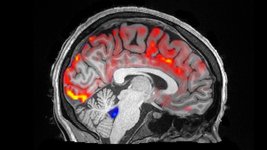

Brain-cleaning sleeping cap gets US Army funding